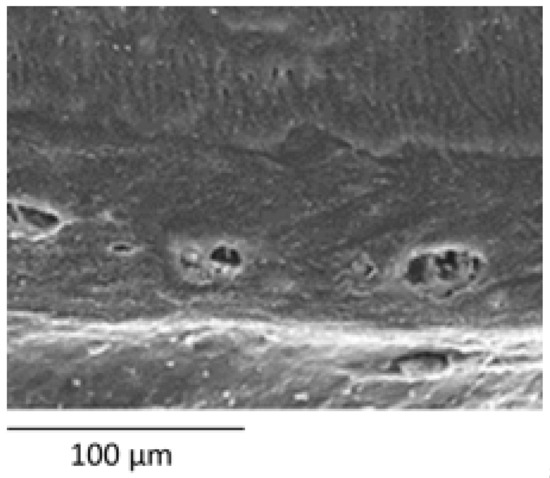

In the dentin, a generalized tissue disintegration and heterogeneity is observed with a decrease in the number of tubular dentin tubules, alteration of the diameter or tubular size, interglobular dentin and atubular areas (Figure 3). The appearance of the dentin was anomalous, with some samples showing dentin with a globular or cerebroid appearance. Significant differences were found in all the dentin points analysed compared to the control group (p < 0.001), with a higher frequency of alterations being observed in the OI group.

Figure 3.

Dentin. SEM photomicrographs at original magnification of 1000×. Superficial dentin (a–d) of a control tooth (a), dentin with mild involvement and alteration in the direction of the dentin tubules (b), dentin with moderate involvement, heterogeneity in the diameter and direction of the dentin tubules and cerebroid appearance (c) and severely affected dentin, atubular amorphous tissue with a cerebroid appearance (d). Middle dentin (e–h) of a control tooth (e) without affectation, with mild affectation (f) with heterogeneity in the diameters of the dentinal tubules, moderate with partial obliteration of the dentinal tubules (g) and severe affectation with the presence of amorphous atubular tissue (h). Deep dentin (i–l) of a control tooth (i) with homogeneity in direction and tubular diameter, mildly affected dentin (j) presenting slightly irregular diameters, moderately affected dentin (k) with the presence of giant tubules and heterogeneity in the diameter of the dentinal tubules and severely affected dentin (l) practically atubular and with an amorphous appearance. Pulpar dentin (m–p) of a control tooth (m) without alterations, of a tooth with slight alterations (n) with slight discrepancies in the tubular diameter, of a tooth with moderate alterations (o) with a decrease in the tubular pattern and of a tooth with severe alterations (p) with an atubular and cerebroid pattern.

The dentin adjacent to the pulp was found to be altered in 92% of the teeth with OI, being severe anomalies in 56% of the occasions, and less frequently moderate or mild. Severe anomalies are more frequent in OI-III than in OI-I or OI-IV, without finding this difference significant (Figure 3m–p and Figure 4) (p value = 0.249).

Figure 4.

Dentin. SEM photomicrograph with a magnification of 500×. Pulpar dentin from a subject with OI-I showing an inclusion of giant ovoid structures in the pulpar dentin.

Dentin has been the most studied dental structure in DGI-I and therefore the one in which most signs of structural anomaly have been described. Regarding the aetiology of dentin alterations, Majorana et al. [16] established that dentin anomalies are possibly a consequence of odontoblast dysfunction, and Lygidakis et al. [17] hypothesized that tubular obliteration is due to mineralization. Multiple investigations have described ultrastructural findings of dentin [16,17,19,24,25,26,29,31,32,33], which can be summarized in the presence of irregular dentinal tubules with alterations in their direction and the presence of both giant and obliterated tubules with circular areas of intertubular matrix without calcification. Similar ovoid areas embedded in dentin have been observed in studies in type II DGI, but it is unclear whether they are unmineralized areas or giant or irregular tubules that have fused together [34]. In addition, the alternation of areas of apparently normal dentin and regions with abnormal dentin has been described. These findings are consistent with our results, in which we found very similar images of varying severity in the four dentin points examined, corresponding to the presence of dentin tubules with a very heterogeneous pattern, with changes in tubular diameter, reduction in tubular density with the presence of atubular regions or with remnants of obliterated tubules, presence of giant tubules and, in the most severe cases, images of totally dysplastic, amorphous and atubular dentin with a globular or cerebroid appearance, which is similar to the findings previously described by other authors.

Malmgren and Lindskog [18] created a dysplastic dentin scale through clinical–radiographic assessment; their findings indicated that the dentin presents greater dysplasia in the circumpulpar area than in the mantle dentin. In addition, they did not find differences in affectation between the primary and permanent dentition. De Coster [28] and Hall et al. [10] analysed the dentin at different depth points, establishing that the mantle dentin and the first layer of tubules is apparently normal, ending abruptly in a zone parallel to the UAD in the which obliterated tubules are found and from which normal and dysplastic or atubular areas alternate. Our data indicate that all the teeth show dentin involvement in at least one point of their extension. Regarding our results, based on the depth of analysis, the dentin closest to the DEJ is the least frequently altered in subjects with OI (40%), being followed by a layer of dysplastic dentin in all cases, leaving passage to the deep and pulpar dentin altered in 84% and 92% of cases, respectively.